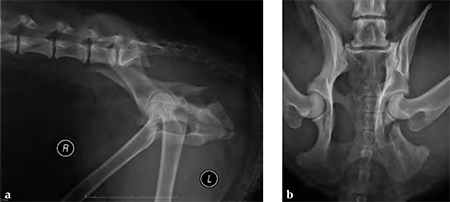

A 4-year-old Gordon setter suffered a road traffic accident and sustained multiple pelvic fractures.

A 7-hole 3.5 mm LC-DCP was applied and two screws were inserted into the sacral body to improve fixation strength in the cranial ilial segment. This bone is quite thin thus note that the screws #1 and #2 are quite short, screws #3 and #4 are the sacral screws and are much longer; the fracture is between screws #4 and #5 (see figure 4a-b)). The opacity on midline in the x-rays is a urinary catheter.